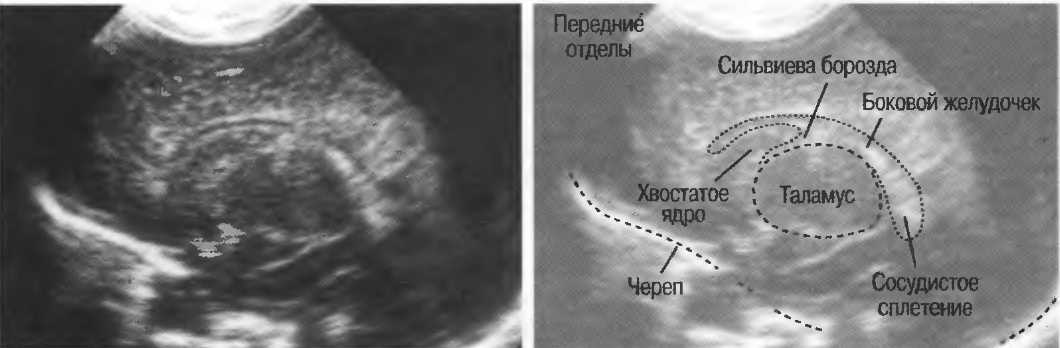

3. Ультразвуковые исследования в педиатрии. Для детей необходим датчик с частотой 5 МГц с глубиной фокусировки на 5-7 см. При исследовании мозга новорожденного используется секторный датчик с частотой 7,5 МГц с глубиной фокусировки на 4-5 см (этот датчик также используется для исследования яичек и структур шеи у взрослых).